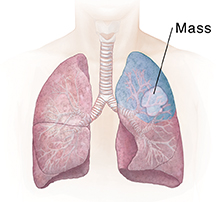

| Segment resection removes a larger part of a lobe. |

A lung mass or tumor

If a tumor has been found in the lung, a tissue sample (biopsy) can be removed. This piece of abnormal tissue is tested in a lab to find out if the growth is not cancer (benign) or is cancer (malignant). The tissue near the tumor can also be examined to see if the tumor has spread. If the tumor needs to be removed, its size, location, and spread determine how much of the nearby lung also needs to be removed. Removing part or all of a lung is called a lung resection.